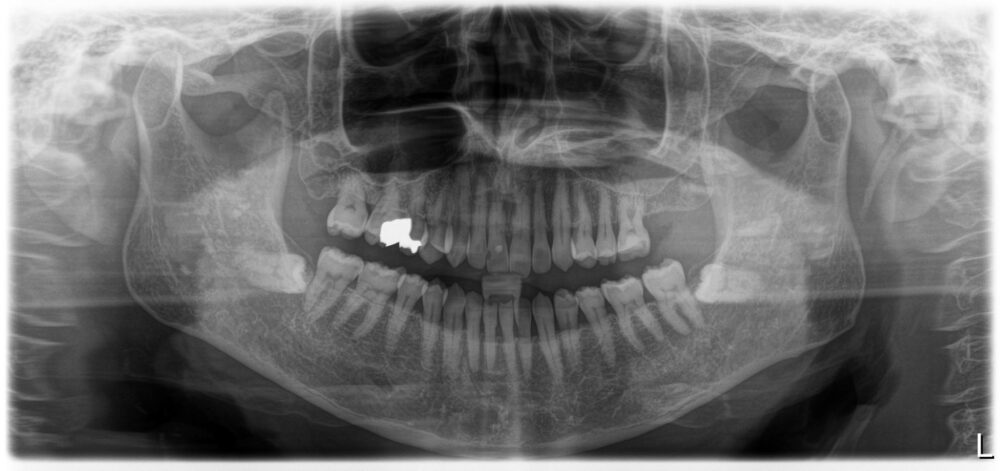

症例2

治療前

| 主訴 | 左上奥歯痛い |

| 診断 |

左上6歯根破折 |

| 治療内容 | 左上6インプラント抜歯即時埋入 |

| 年齢・性別 |

66歳、女性 |

| 治療期間 |

6ヶ月 |

| 治療費用 | 診査診断¥22000+一次オペ(アストラ)¥330000+GBR¥110000+¥上部構造¥143000 合計¥605000 |

| リスク・副作用 | インプラント周囲炎、上部構造の緩み |